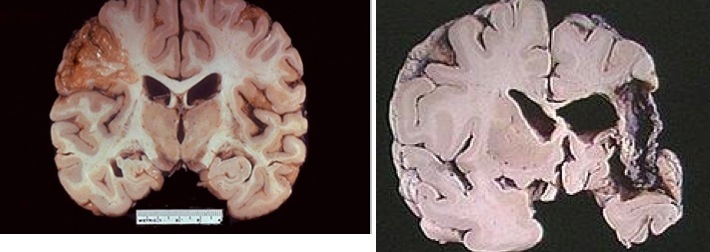

Ischemic stroke

Cerebral Infarct

Intraparenchymal/intracerebral hemorrhage

C&C: